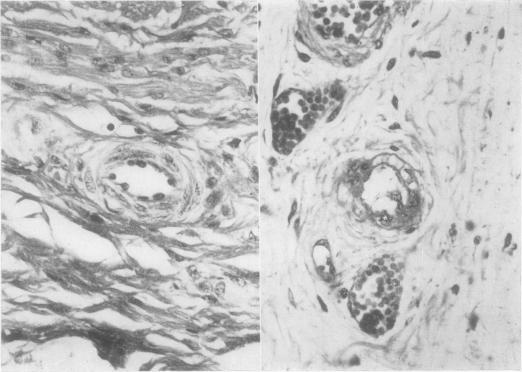

Experimental colibacillary (Escherichia coli) enterotoxemia as described in this report mimics natural edema disease both clinically and in gross pathology. The histopathology is characterized by accumulations of non-inflammatory edema and by arteriopathy. The smaller arterial and arteriolar changes recorded here are similar to those described in natural edema disease. The vascular changes described in recovered cases of experimental colibacillary enterotoxemia concur with those reported in so-called subacute and chronic edema disease. The arteriolar changes that occur in colibacillary enterotoxemia of swine are comparable to those associated with hypertension. Thin sections of cerebral cortex from four pigs with acute experimental edema disease were examined by electron microscopy in an attempt to demonstrate brain edema. Sections from one pig taken during the convulsive phase of disease revealed dilatation of perivascular glial processes. However, examination of sections taken from three other pigs during an earlier phase of the neurological disturbance revealed no significant lesions. We were unable to ascertain the role of brain edema in the pathogenesis of the nervous system disturbance in these experiments.

本报告中描述的实验性大肠杆菌肠毒血症在临床和大体病理学方面均模拟了自然水肿病。组织病理学特征为非炎性水肿积聚和动脉病变。此处记录的较小动脉和小动脉变化与自然水肿病中描述的变化相似。实验性大肠杆菌肠毒血症康复病例中描述的血管变化与所谓的亚急性和慢性水肿病中报道的变化一致。猪大肠杆菌肠毒血症中发生的小动脉变化与高血压相关的变化相当。对4头患有急性实验性水肿病的猪的大脑皮质薄切片进行了电子显微镜检查,试图证明脑水肿。在疾病惊厥期取自1头猪的切片显示血管周围神经胶质细胞突起扩张。然而,对另外3头猪在神经功能障碍早期阶段所取切片的检查未发现明显病变。在这些实验中,我们无法确定脑水肿在神经系统功能障碍发病机制中的作用。